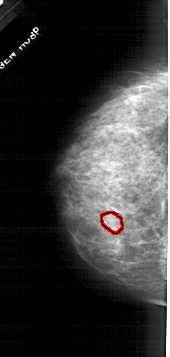

A_1712_1.LEFT_MLO

LEFT_MLO LINES 5491 PIXELS_PER_LINE 2686 BITS_PER_PIXEL 12 RESOLUTION 43.5 OVERLAY

FILE: A_1712_1.LEFT_MLO.OVERLAY

TOTAL_ABNORMALITIES 1

ABNORMALITY 1

LESION_TYPE MASS SHAPE OVAL MARGINS OBSCURED

ASSESSMENT 3

SUBTLETY 3

PATHOLOGY BENIGN

TOTAL_OUTLINES 1

BOUNDARY